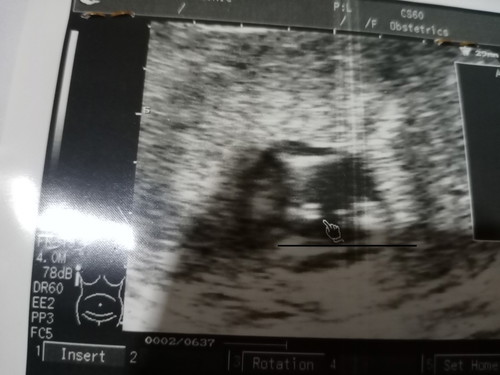

หมอซาวตอน14วีค. บอกว่าชาย มีสิทธิ์เป็นหญิงได้ไหมคะ. หมอว่าห็นไข่ไม่ชัด ปล.ลูกคนแรกชาย คนที่2อยากได้หญิงค่ะ